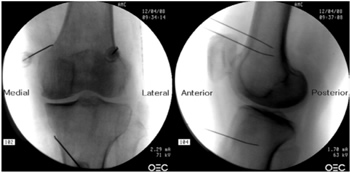

25. El-Hakeim EH, Elawamy A, Kamel EZ, Goma SH, Gamal RM, Ghandour AM, et al. Fluoroscopic guided radiofrequency of genicular nerves for pain alleviation in chronic knee osteoarthritis: A single-blind randomized controlled trial. Pain Physician. 2018;21(2):169-77.

37. Arican S, Hacibeyoglu G, Akkoyun Ö, Uzun ST, Reisli R. Fluoroscopy-guided genicular nerves pulsed radiofrequency for chronic knee pain treatment. Agri. 2020;32(1):38-43.